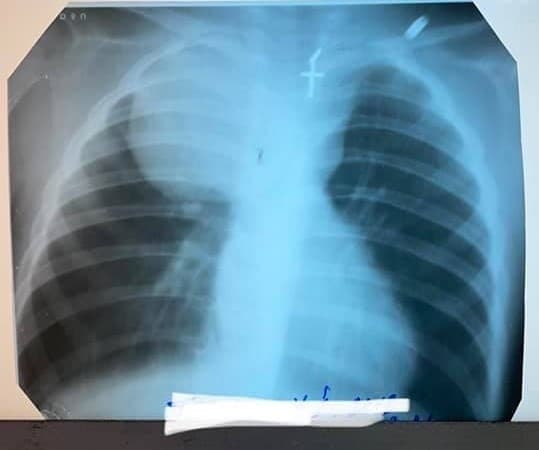

Із лютого цього року батьки дворічного пацієнта Львівської обласної дитячої клінічної лікарні ОХМАТДИТ помітили у нього кашель, задишку і осиплість голосу. Сімейний лікар родини почув дистанційні хрипи, зробив рентген і побачив утворення у правій легені. Хлопчика скерували відразу в Інститут раку до Києва, але батьки вирішили приїхати до ОХМАТДИТу.

У медзакладі повідомляють, що малюка дообстежили: зробили КТ і аналіз крові на онкомаркери. Аналіз показав, що злоякісного процесу немає. Після консультації̈ з онкологом хлопчика прооперували. Лікарі зрозуміли, що пухлина не дотична до легені, а розташовується у задньому межистінні. Вона стискала трахею і правий головний бронх, зміщуючи органи межистіння – звідки у нього задишка, осиплість голосу.

«Ми спробували видалити пухлину, але це технічно було неможливо, бо величезна пухлина була припаяна до грудної стінки. Перейшли на відкриту торакотомію, тобто через розріз грудної клітки, а з іншого боку підсвічували собі все камерою. Пухлину вдалося повністю видалити», – розповідає торакальний хірург Олександр Колодій.

Гістологія підтвердила: у малюка була гангліоневрома – доброякісне утворення. Такі пухлини дуже рідко трапляються. За три роки – це друга дитина з таким діагнозом у лікарні ОХМАТДИТ.